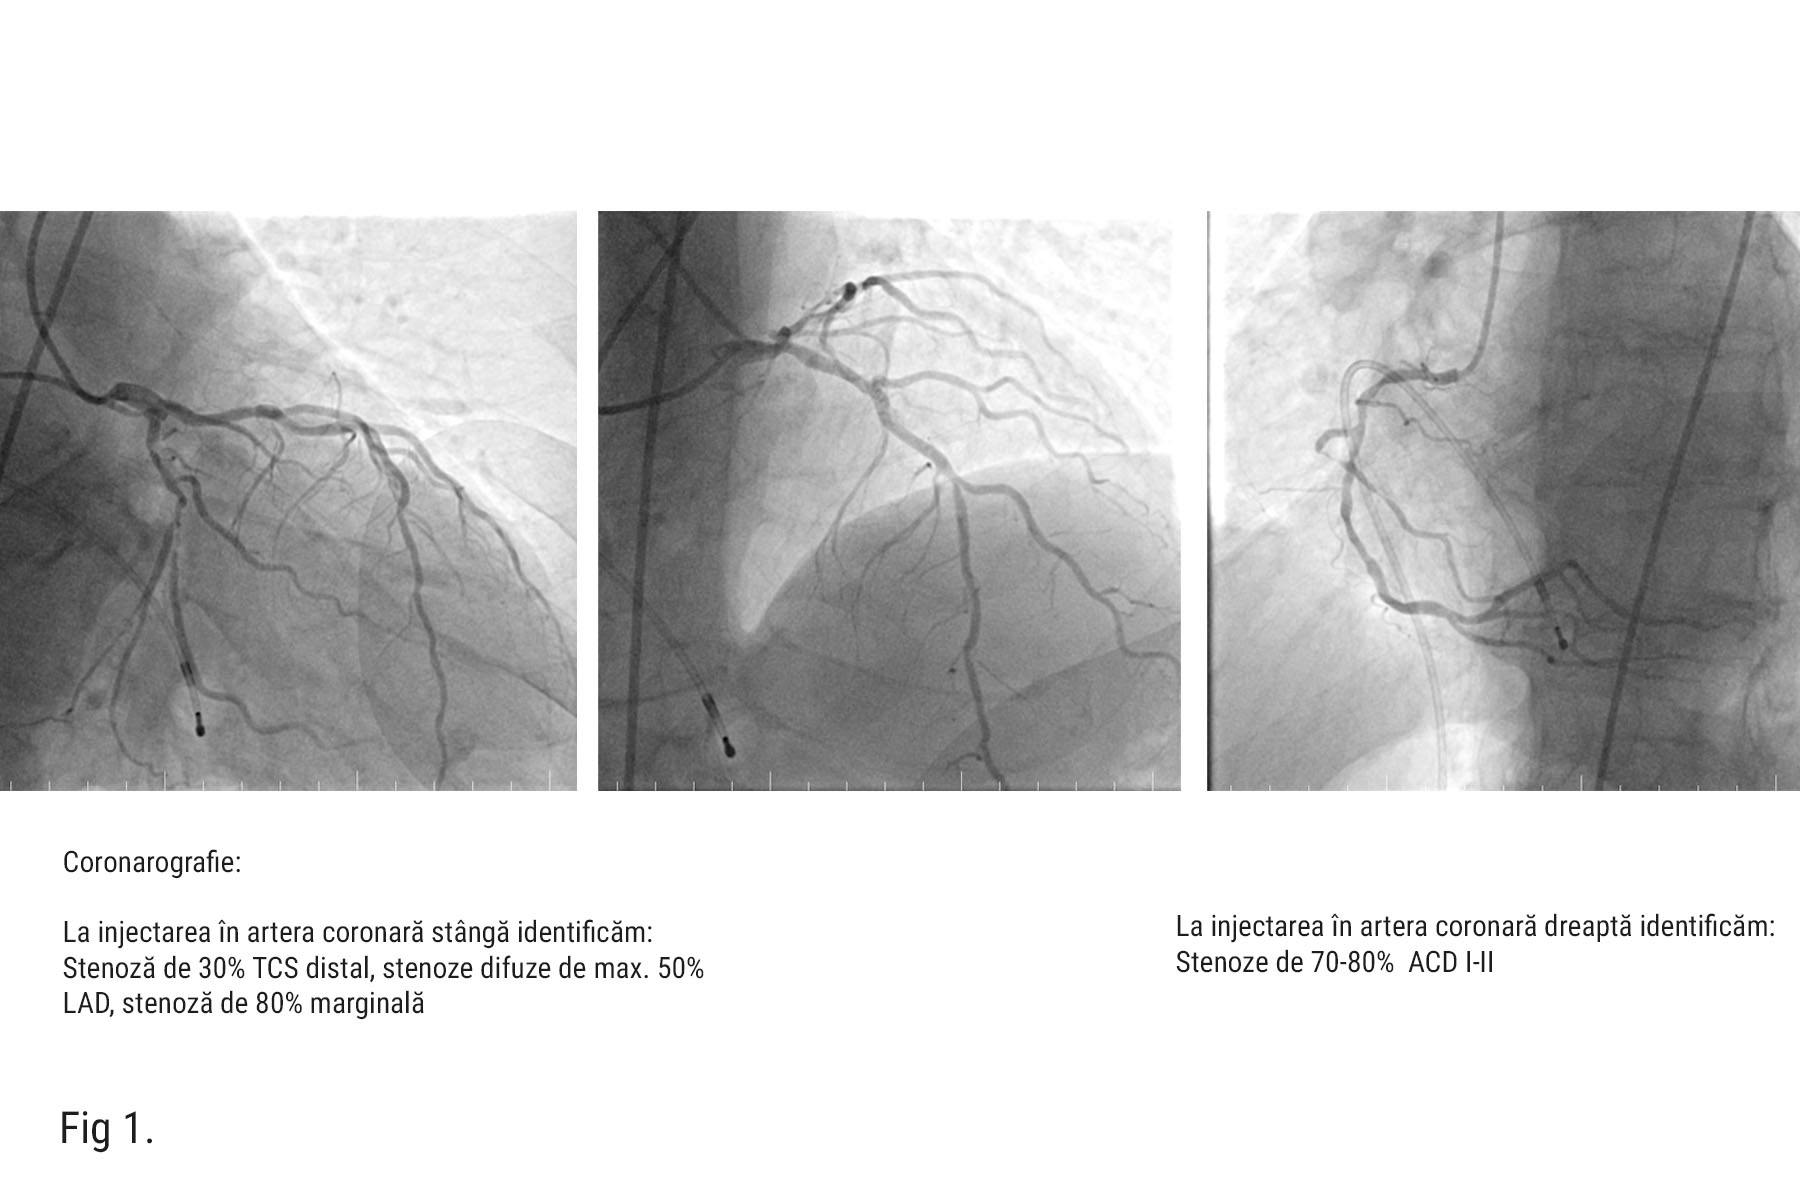

Pe parcursul procedurii, dr. Nicolae Cârstea, a efectuat și o coronarografie care a evidențiat stenoze coronariene semnificative (70-80% în ramurile marginală și ACD (Fig. 1).

Având în vedere boala cronică de rinichi, s-a decis amânarea angioplastiei coronariene o lună după procedura de TAVI. După această perioadă, pacientul s-a prezentat la MONZA ARES Constanța – HEKA Hospital unde dr. Nicolae Cârstea, a efectuat angioplastie coronariană cu două stenturi farmacologice active pe ACD si un stent DES pe ACX către MG I. (Fig. 3 – rezultat final cu stenturi)